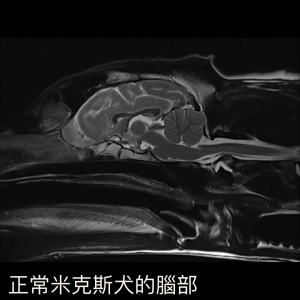

圖二為正常米克斯犬的腦部